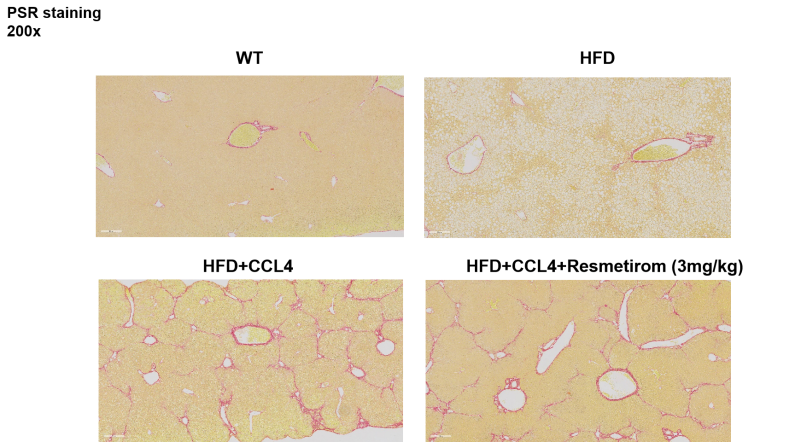

图5 小鼠肝脏病理组织学检测结果:HE染色、NAS评分、ORO染色与PSR染色

4周治疗后,Resmetirom保护了HFD和HFD+CCL4诱导的肝脏脂肪变性和气球样变。蓝色箭头表示脂肪变性,绿色箭头表示小叶炎,黑色箭头表示气球样变。脂肪变性(0-3分)、小叶炎症(0-3分)、气球样变(0-2分)、NAS评分(0-8分)。数据表示为平均值±标准误,n=5。